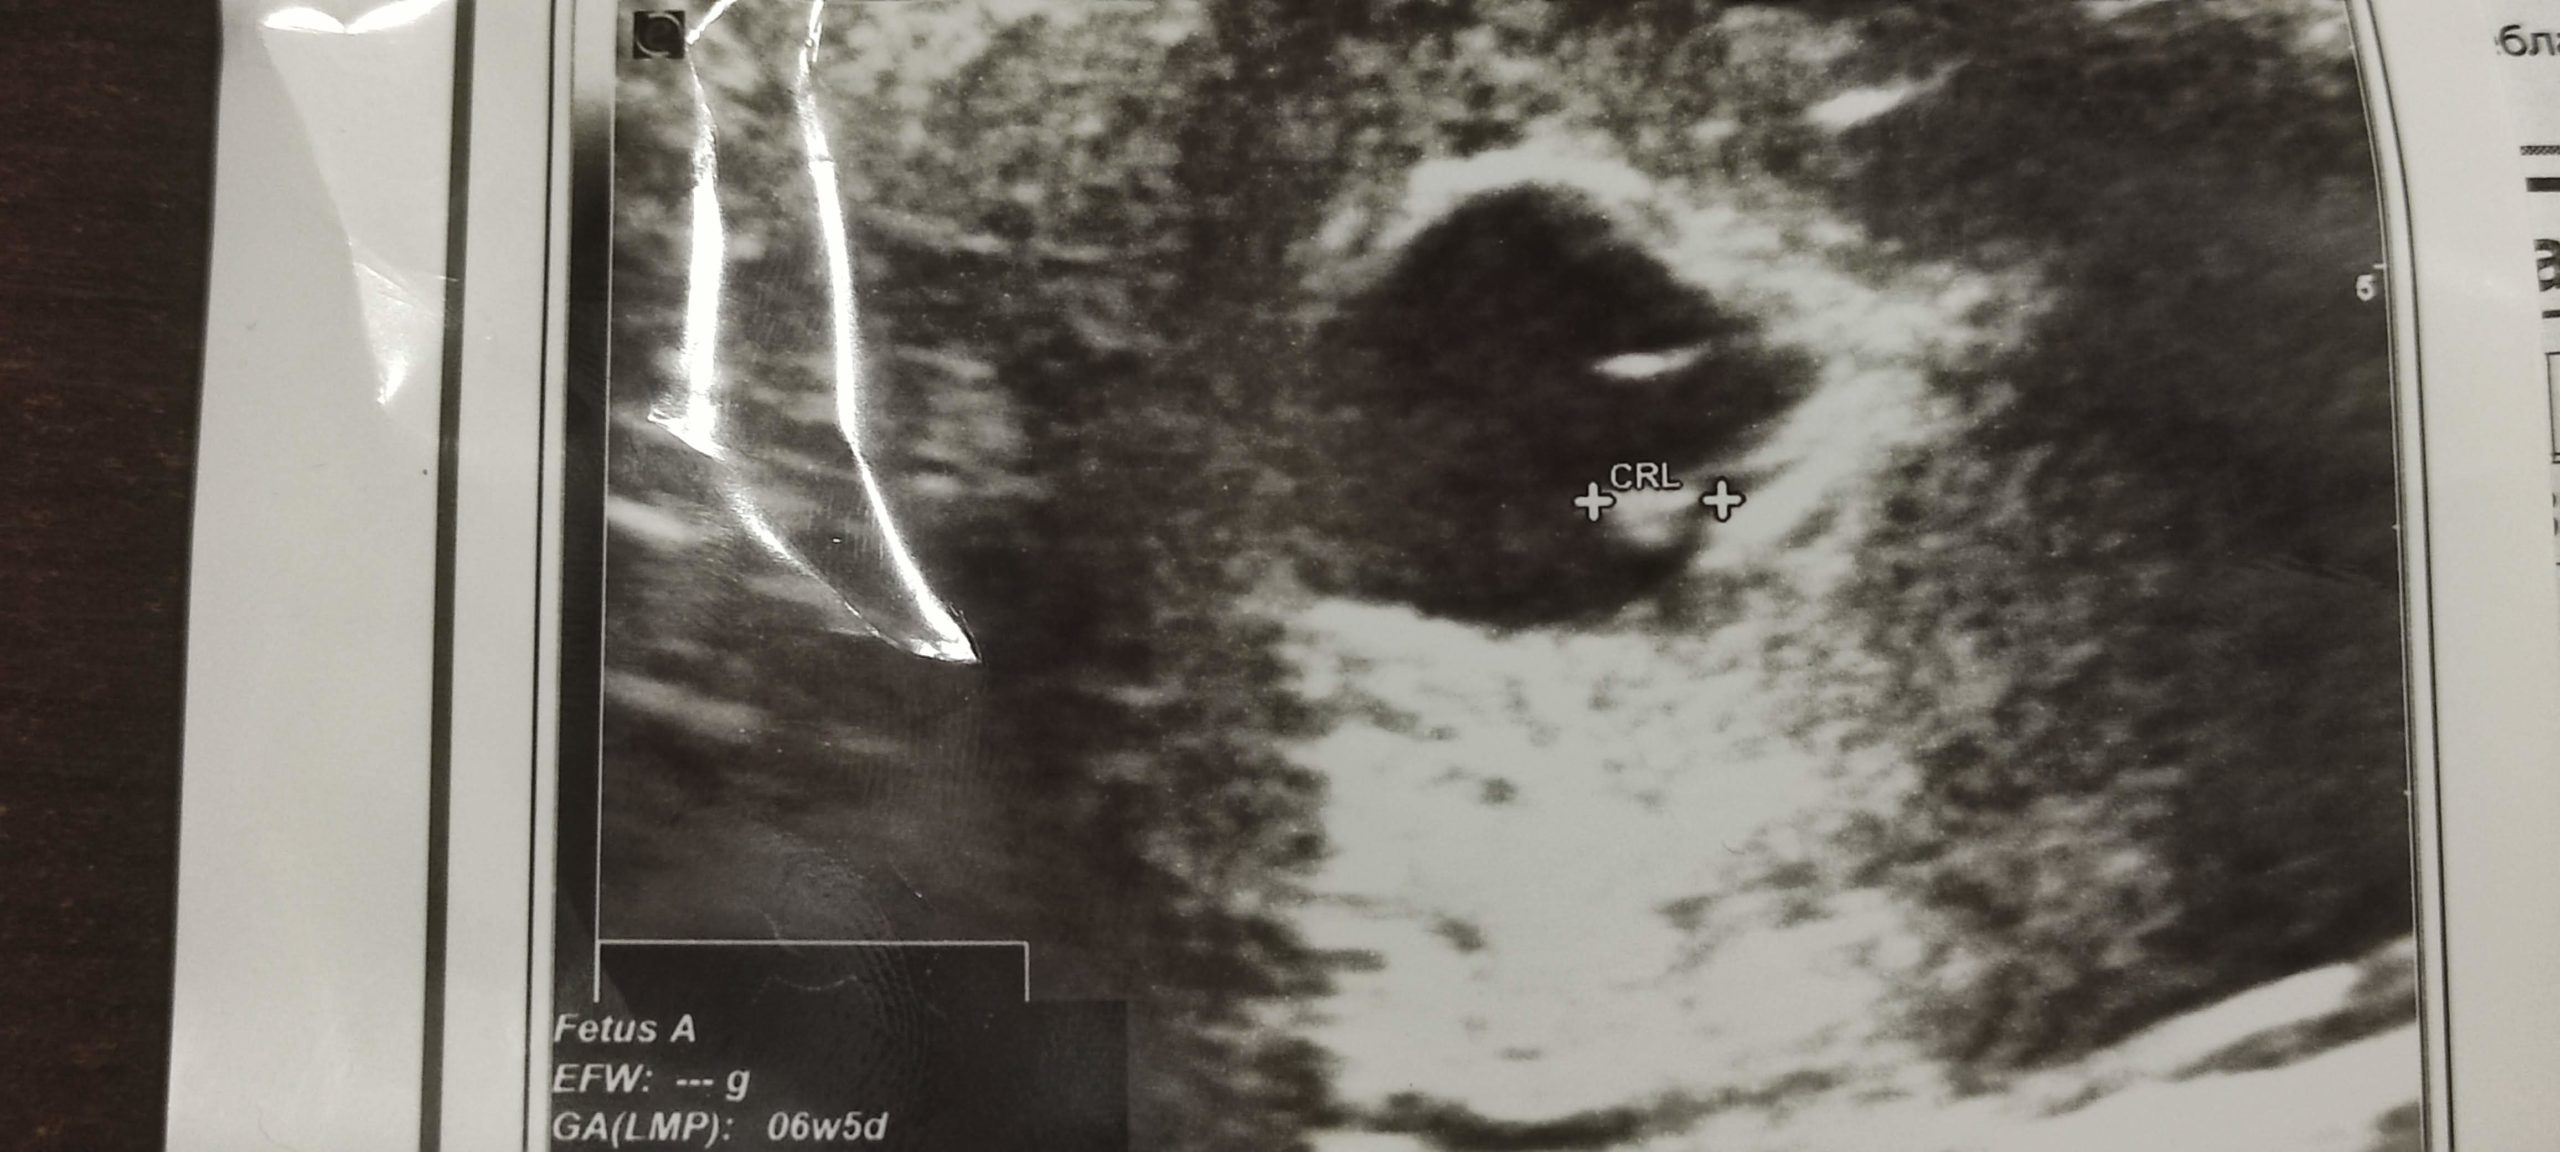

• РОДИ СЕ ОГИ. Е на, каня се от септември месец да пиша за това, но търся муза и така и не писах, но имаме второ детенце, което носи огъня в себе си – Огнян. В ретроспекция съм убеден, че това биха били най-добрите години в живота ми.

Злати е бременна и ще ставаме родители за втори път. Борката още няма идея какво го очаква, сигурно и ние. Последните 2 години си бяха roller coaster, но не мисля, че съм бил толкова щастлив някога. И толкова изморен. Но си струва всеки момент, всеки памперс, всяка усмивка. Мисля, че точно тези моменти са пикът в моя живот в който всичко е просто (макар и аз да го усложнявам многократно в главата си), Борко е щаслив да ме види, бяга да ме прегърне когато му щукне, Злати ме обича с цялото си сърце и наистина разчитаме мега много един на друг. Аз съм здрав. Ще чета този пост след още 8 години да видим колко съм бил прав.